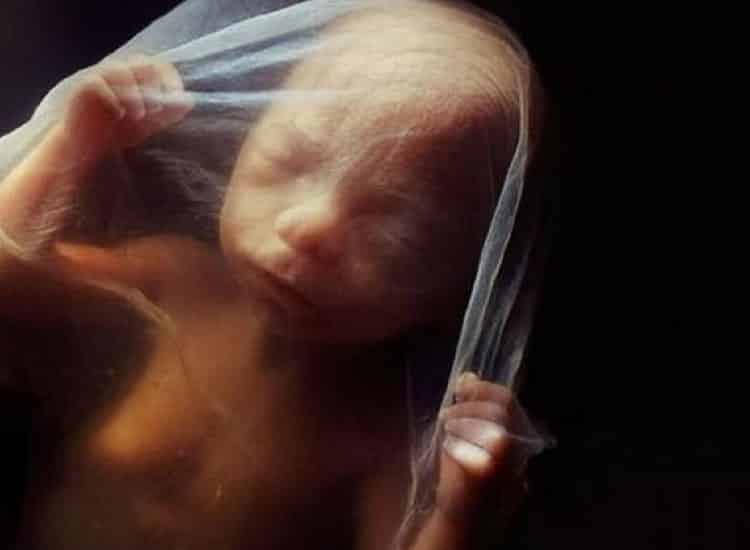

Com vinte e quatro semanas

Aos 6 meses de gestação o bebê já está bem formado